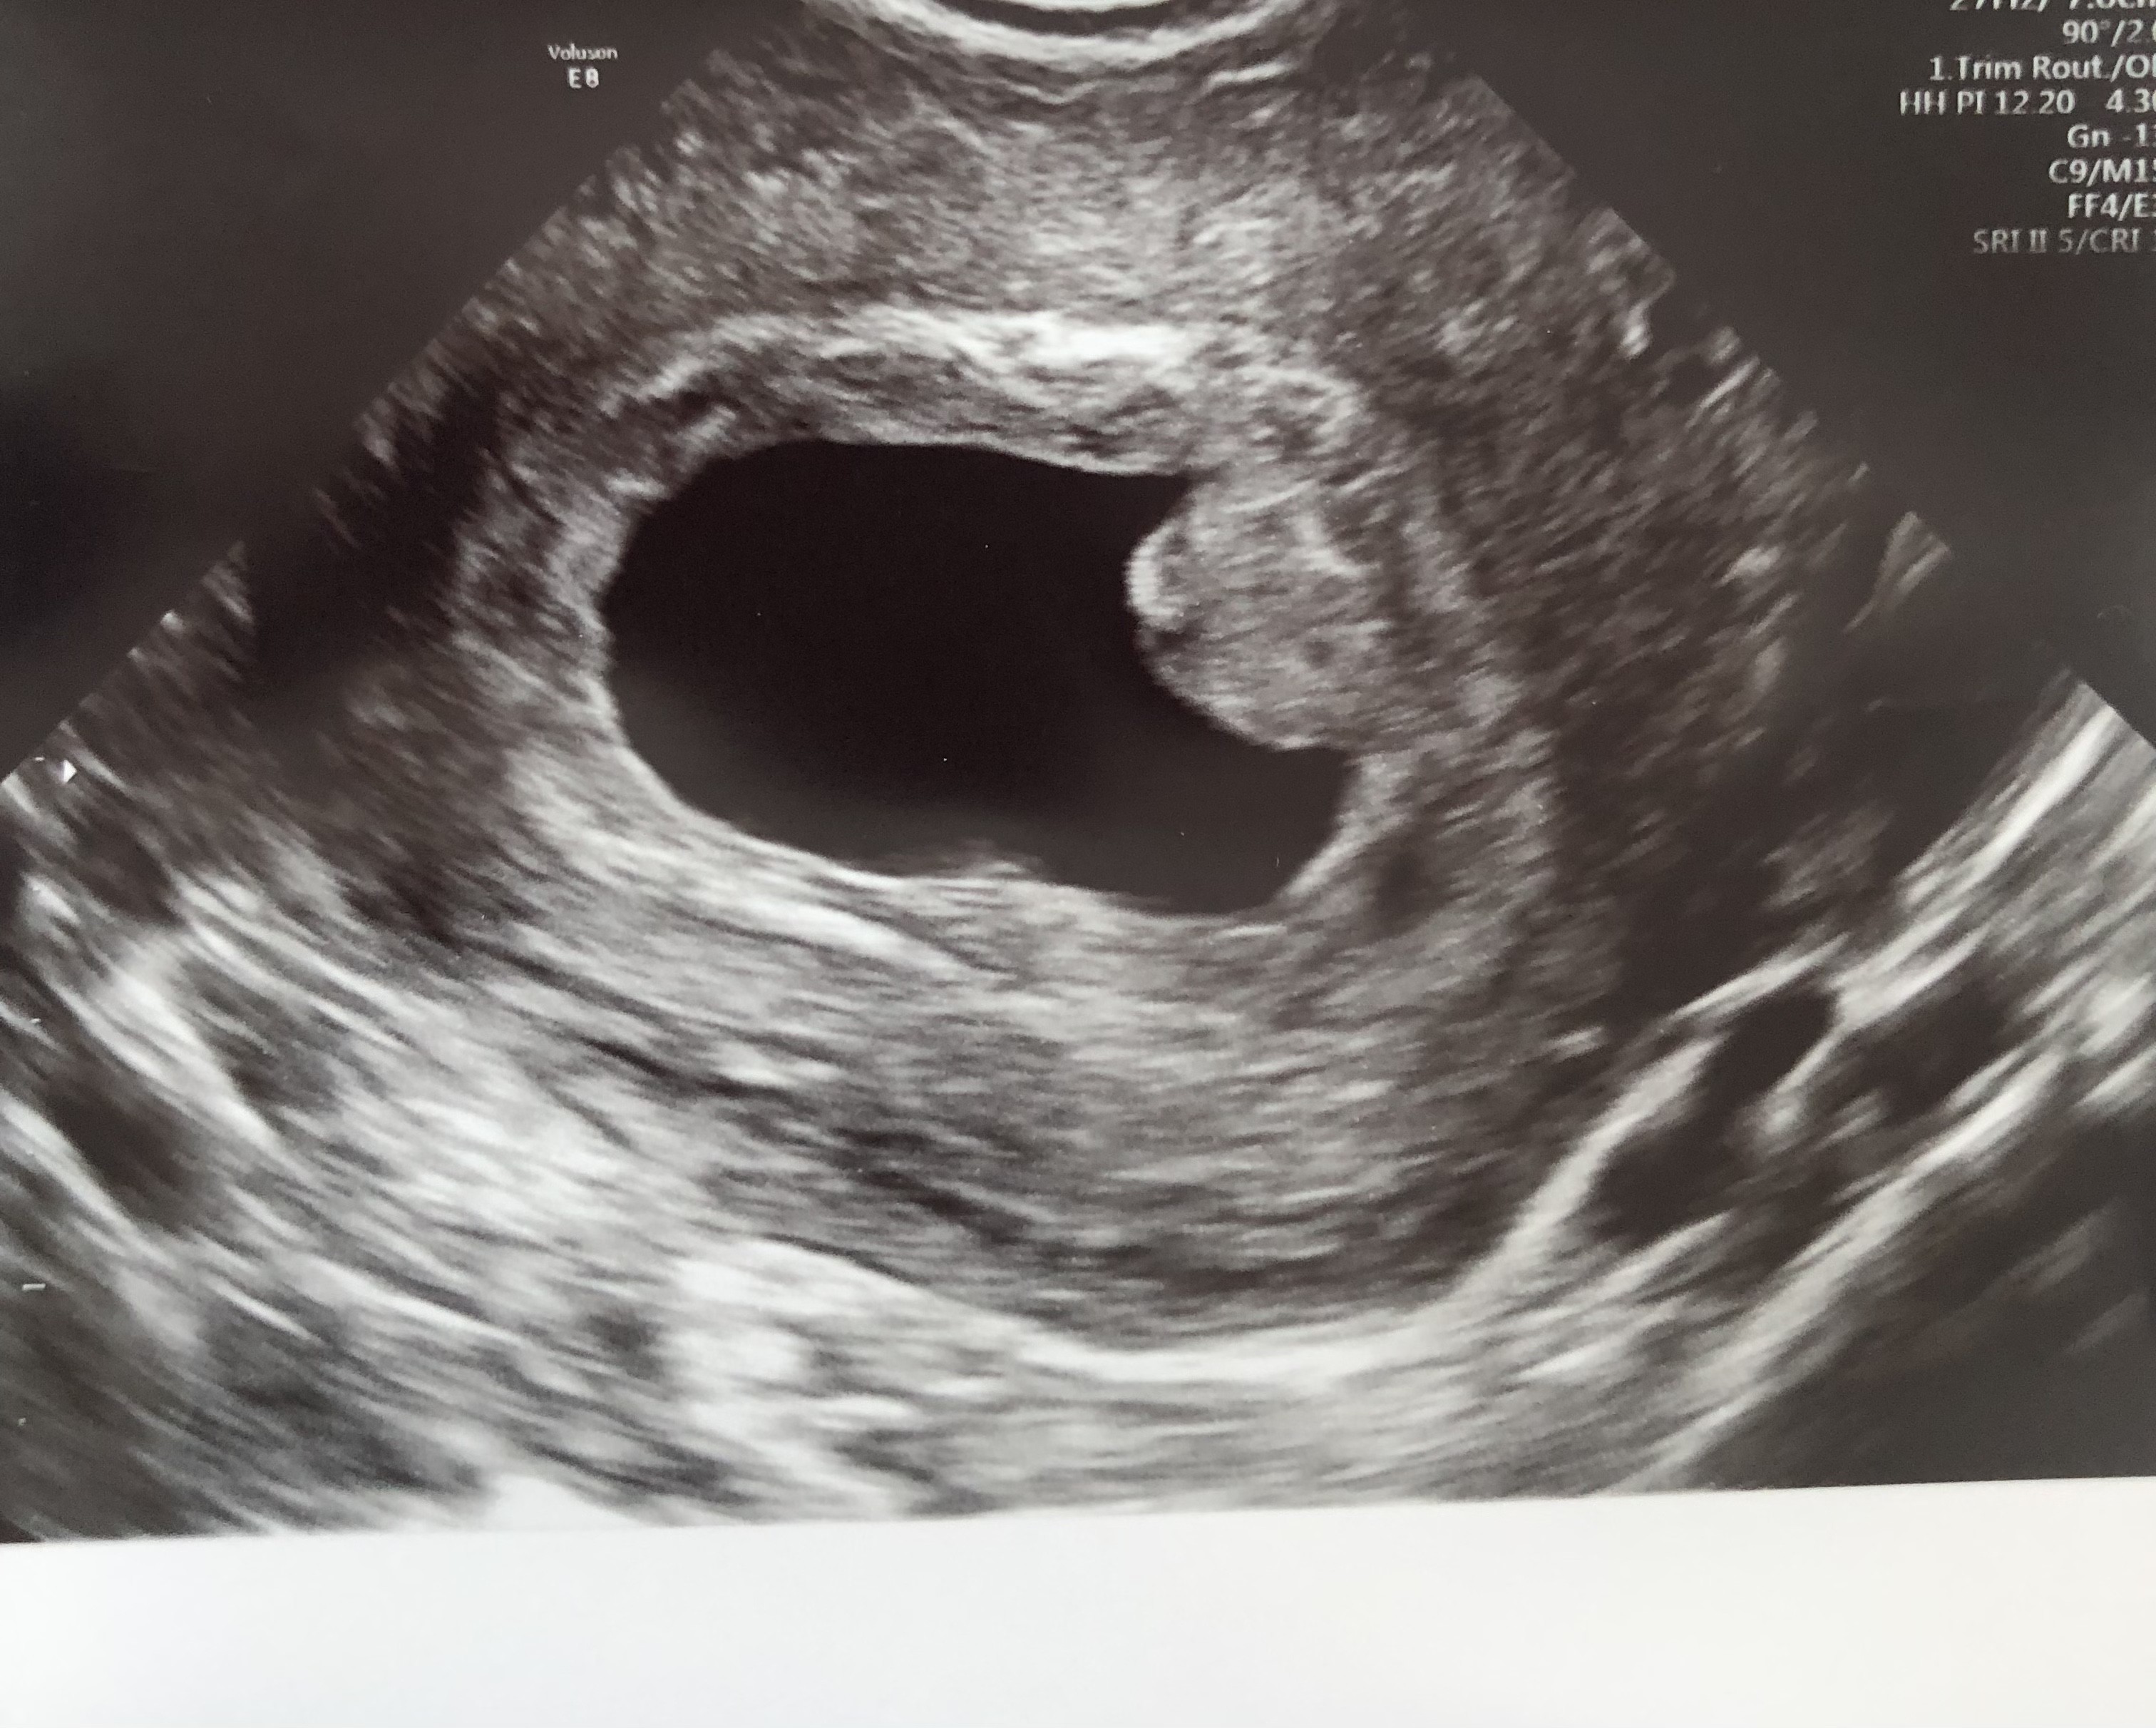

Czy będzie zarodek z bijącym sercem?

Hej,

Z OM wychodzi 7 tydzień 3 dzień. Ginekolozka powiedziała, ze ciąża wyglada dziwnie, ze nic z tego nie będzie i dała skierowanie do szpitala z podejrzeniem poronienia zatrzymanego. Kazała przyjść za tydzień na usg. Czy naprawdę nie ma już szans?

@Lily123 , obawiam się, że kiepsko to wygląda.